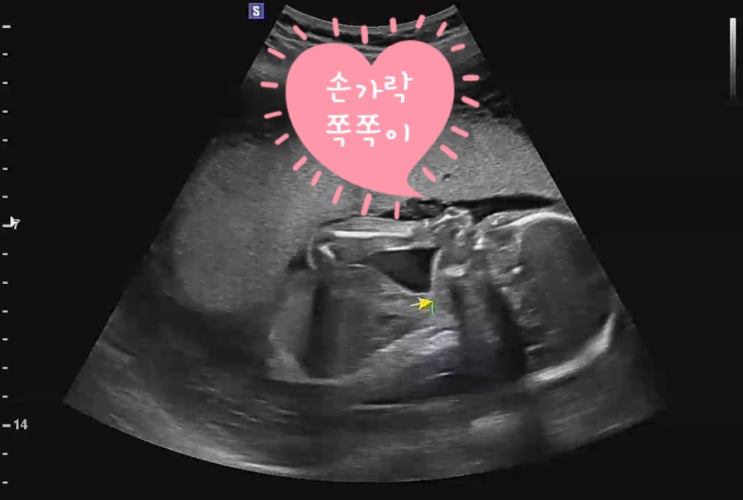

[임신일기]15 신생아빨래 32주차초음파 임신31주차~임신32주차

레인부츠 크기가 된 31주차~ 두 달도 안남았다고 생각하니 이제 슬~슬~ 아기 맞이 준비를 해야한다 아가를 ...